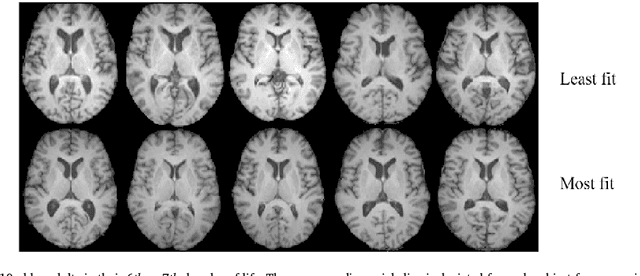

Abstract:Disease in the brain is often associated with subtle, spatially diffuse, or complex tissue changes that may lie beneath the level of gross visual inspection, even on magnetic resonance imaging (MRI). Unfortunately, current computer-assisted approaches that examine pre-specified features, whether anatomically-defined (i.e. thalamic volume, cortical thickness) or based on pixelwise comparison (i.e. deformation-based methods), are prone to missing a vast array of physical changes that are not well-encapsulated by these metrics. In this paper, we have developed a technique for automated pattern analysis that can fully determine the relationship between brain structure and observable phenotype without requiring any a priori features. Our technique, called transport-based morphometry (TBM), is an image transformation that maps brain images losslessly to a domain where they become much more separable. The new approach is validated on structural brain images of healthy older adult subjects where even linear models for discrimination, regression, and blind source separation enable TBM to independently discover the characteristic changes of aging and highlight potential mechanisms by which aerobic fitness may mediate brain health later in life. TBM is a generative approach that can provide visualization of physically meaningful shifts in tissue distribution through inverse transformation. The proposed framework is a powerful technique that can potentially elucidate genotype-structural-behavioral associations in myriad diseases.